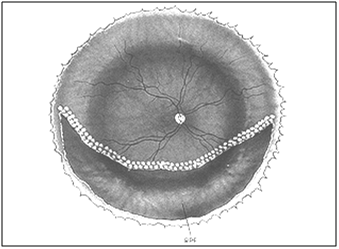

9 cases had a lower break not associated with PVR and of these 3 had additional intrinsic contraction. It was noticed that all cases with recurrent detachment without PVR or those with posterior PVR were confined to the lower half of the retina. Cases with a combined anterior and posterior PVR were more aggressive and involved a total or near total retinal detachment (Figure 1).

Figure 1 Causes of recurrent retinal detachment under silicone oil.